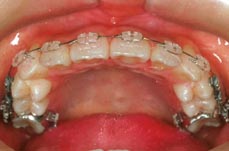

治療後

上顎両側4番を抜歯

下顎両側4番も抜歯